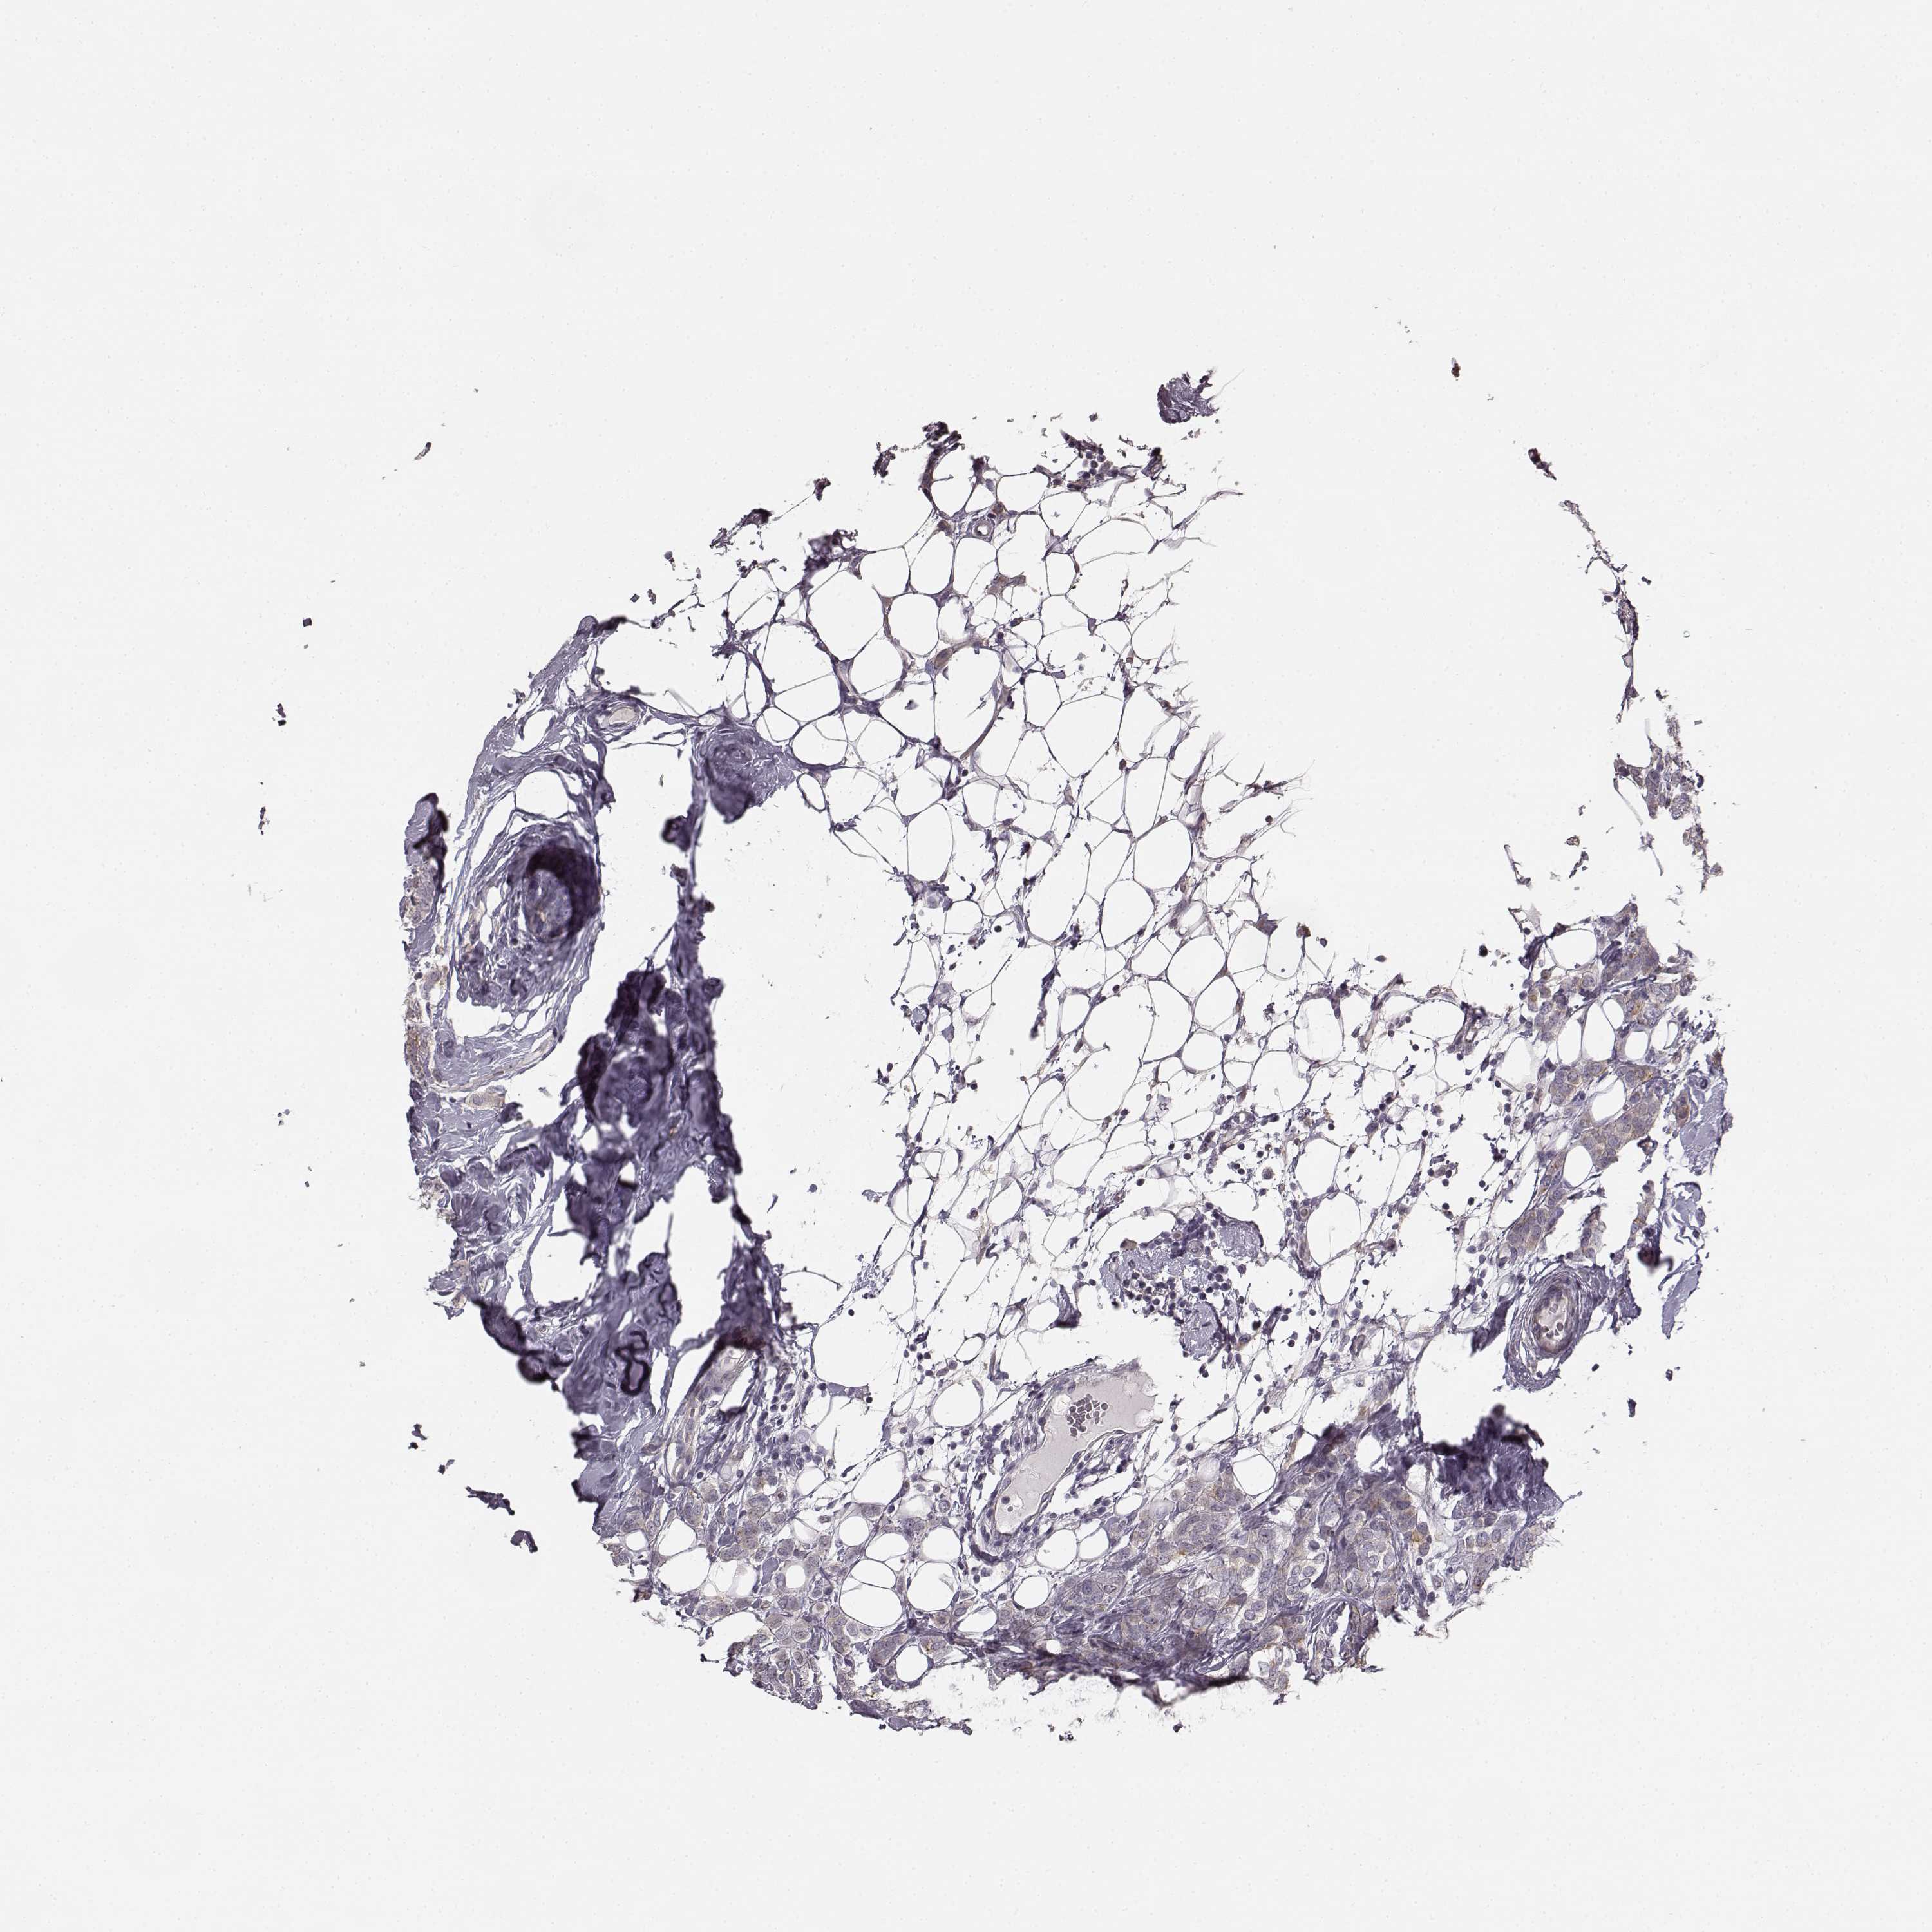

CANCER BREAST CANCER Show tissue menu

BRCA TCGA BRCA VALIDATION PROTEIN EXPRESSION